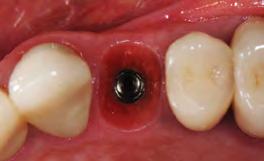

3. Minimally invasive removal of #12 using only a buccal approach mini-flap showing an intact buccal plate with immediate placement of the implant (1 mm below the intact buccal wall) in a screw-retained position. A 3mm buccal gap is measured and a 1.5mm palatal gap.

4. Both the buccal and palatal gaps have been packed with Geistlich Bio-Oss Collagen® hydrated with Gem 21S. I prefer to squeeze Geistlich Fibro-Gide® between thumb and forefinger, prior to placement. A dry-carved piece of Geistlich FibroGide® is in position thinned approximately 2mm with beveling laterally and coronally with a new #15 blade.